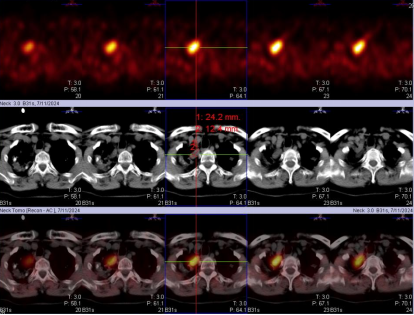

甲状旁腺显像异常图像(考虑甲状旁腺功能亢进):